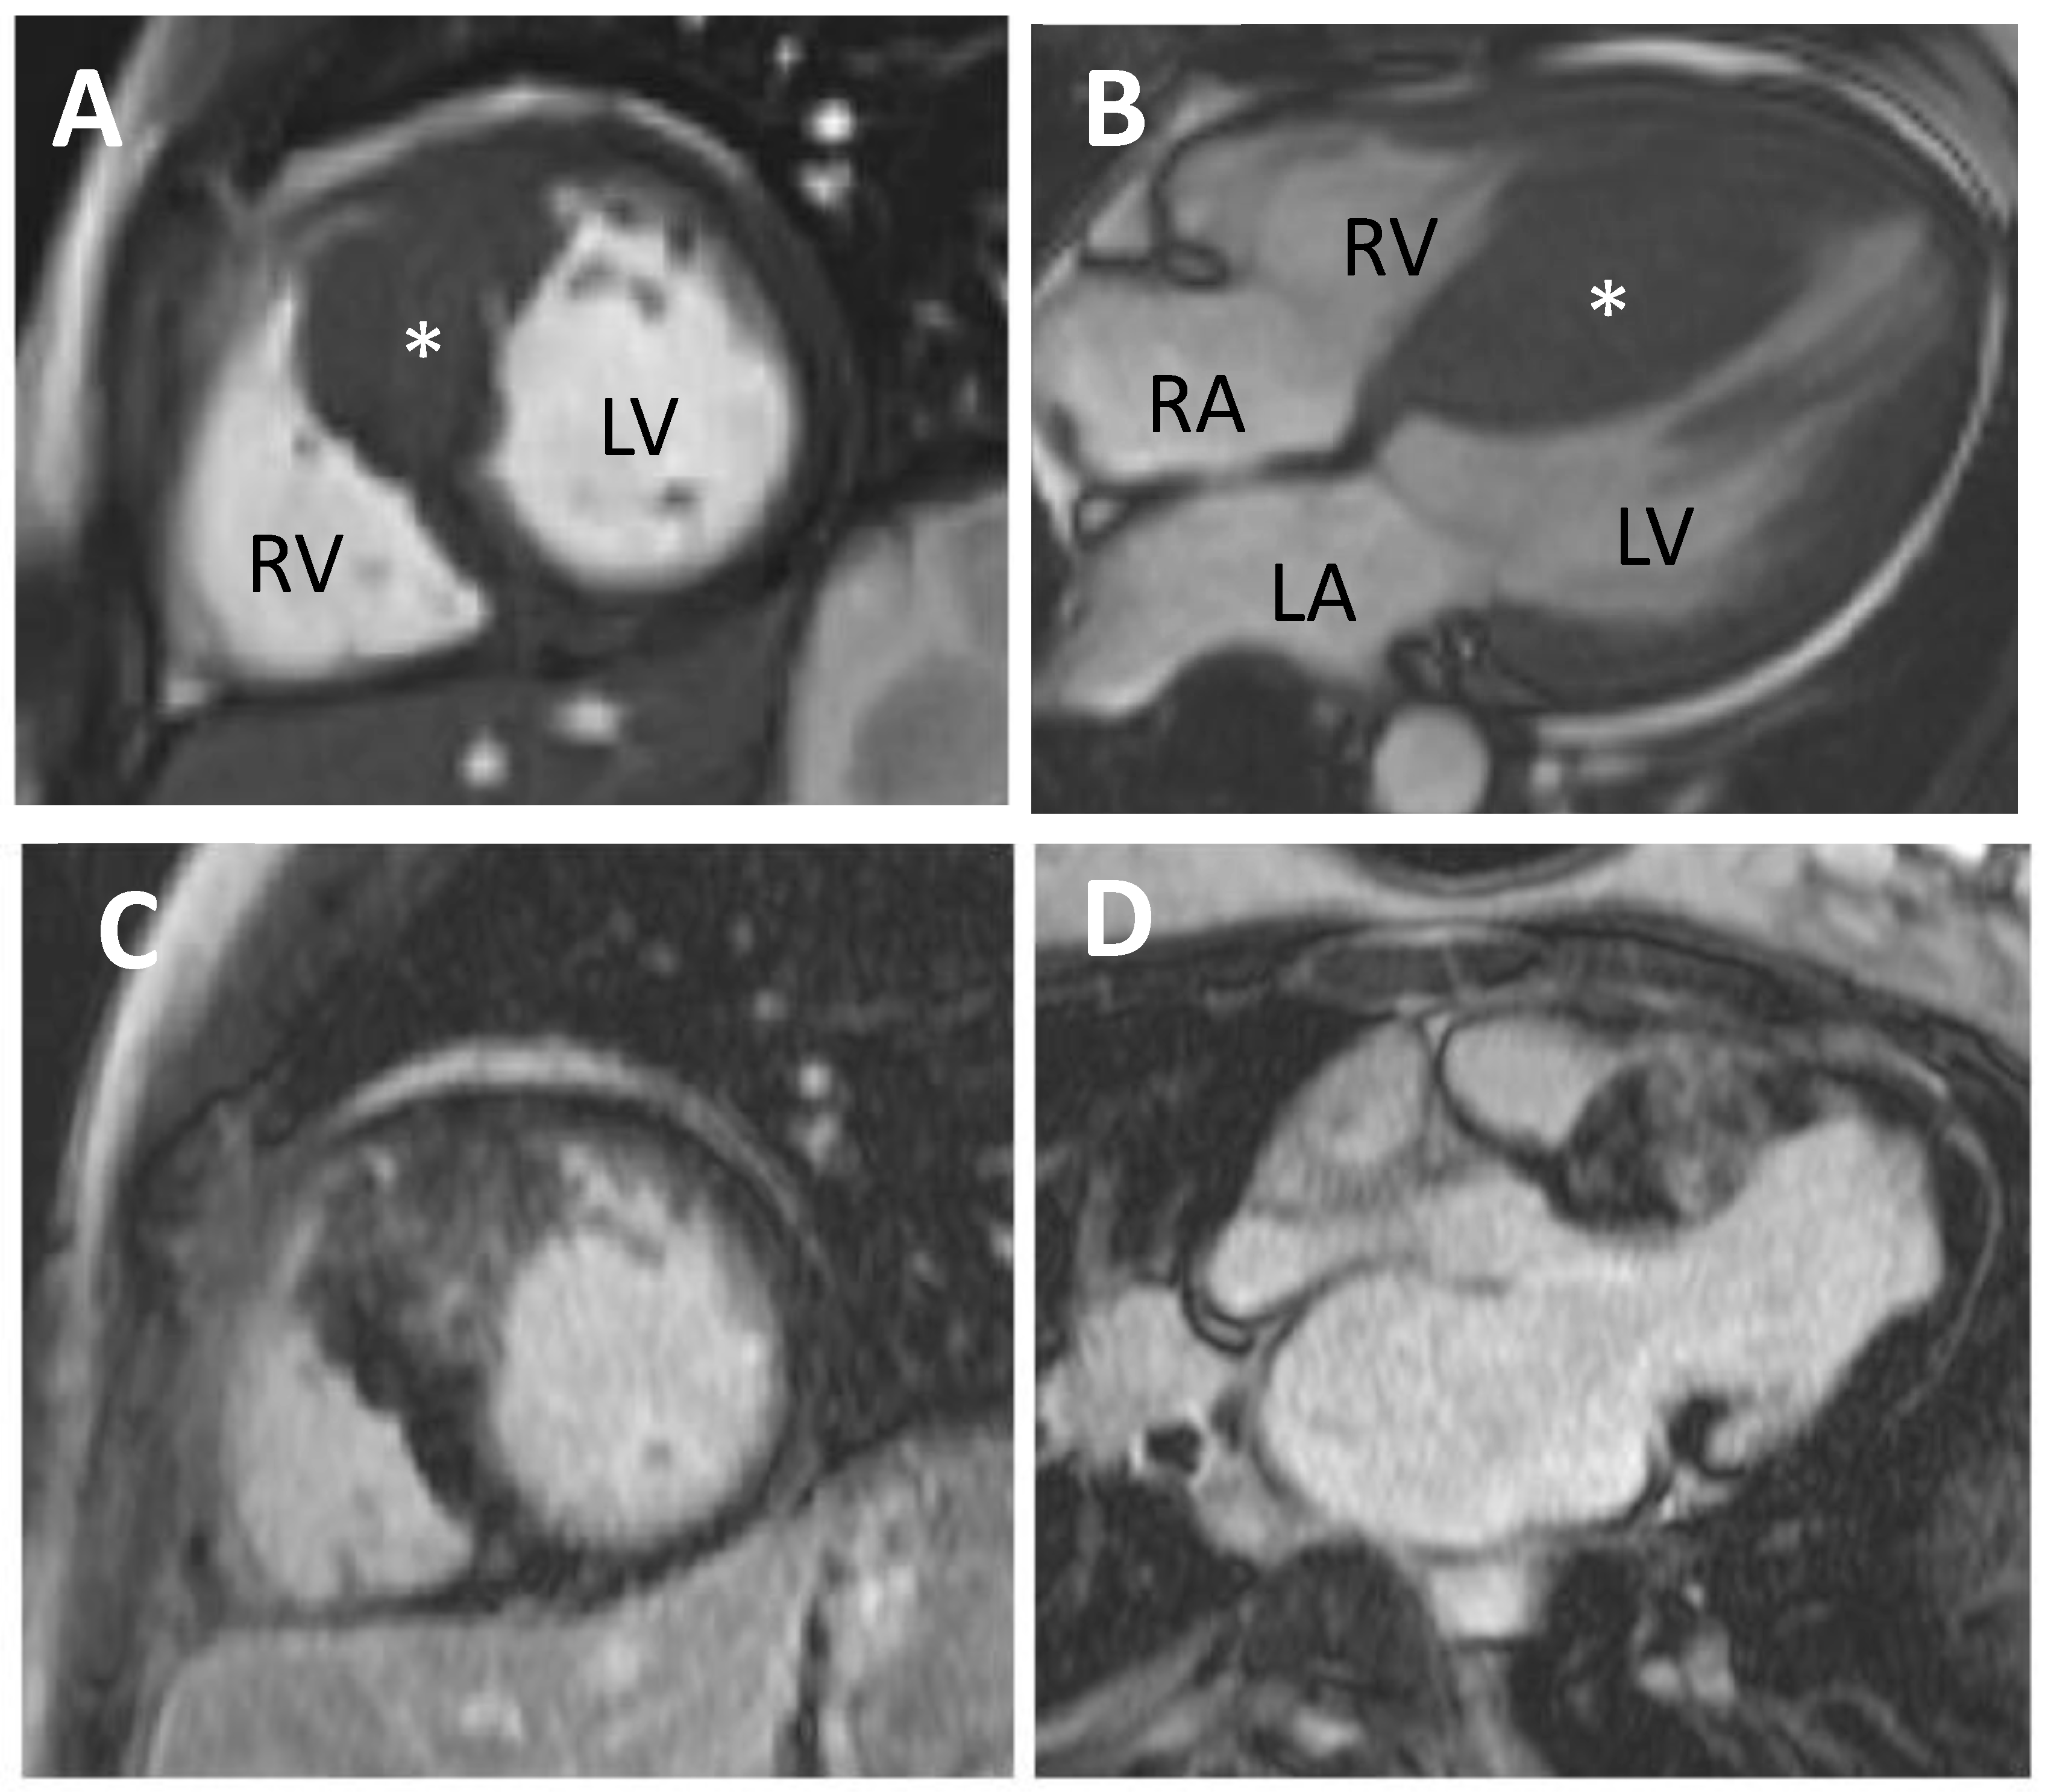

CMR is a helpful diagnostic and risk stratification tool in HCM. It possesses excellent spatial and temporal resolution, allowing accurate assessment of ventricular volumes and anatomical structures (Figure 3). Unlike echocardiography, it is not restricted by poor acoustic windows and is more sensitive in detecting apical or focal HCM. Tissue characterisation with late gadolinium enhancement (LGE) allows detection and quantification of myocardial fibrosis (Figure 3C,D). Fibrosis is present in up to two-thirds of HCM patients [48,49,50]. Gadolinium contrast will accumulate in areas of myocardial fibrosis and is seen as bright tissue on inversion recovery sequences. The presence of fibrosis as assessed via LGE has been found to be a strong independent predictor of SCD, heart failure death, cardiac mortality and all-cause mortality in HCM, making CMR a useful prognostic imaging modality [51,52]. The extent of fibrosis as detected by LGE has also been suggested to be important when characterising risk of adverse outcomes [52]. However, technical variability in LGE quantification exists and is determined by the sequences used, the thresholds set for LGE identification and timing of post-contrast imaging [47]. Until this is standardised, formulating guidelines to aid risk stratification in HCM using LGE will remain a challenge.

Figure 3.

Hypertrophic cardiomyopathy imaged using cardiovascular magnetic resonance (CMR). (A) Short axis through the heart and asymmetrical left ventricular hypertrophy (starred); (B) Four chamber view of the heart; (C) Late gadolinium imaging showing patchy fibrosis of the hypertrophied area; (D) Same heart in the long axis. LV—Left ventricle, RV—Right ventricle, LA—Left atrium, RA—Right atrium.